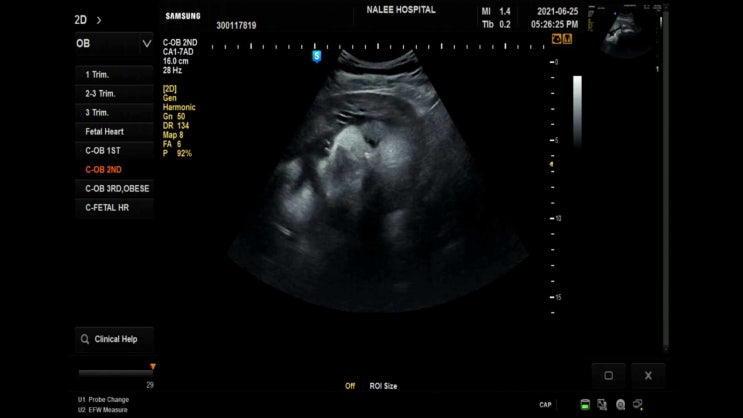

20210625 32주차 9개월 만삭의 시작

출산하고 다시쓰는 출산전일기 8개월때 병원 검진 다녀온 이후로 9개월이 되니 확실히 차이나는건 태동 태...